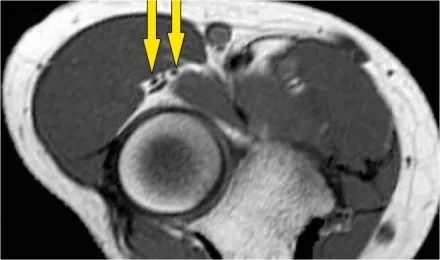

尺神经:在这里,我们看到了肘管内的尺神经。尺骨侧支带的后带形成隧道的底部,而支持带形成屋顶。

该患者有尺神经神经病变。肘管综合征是一种常见的周围神经病变。它产生于肘管内尺神经,其中该神经传递肘管支持带的下方的压缩。

因此,当我们回到图像时,您会发现很难找到神经。任何这些皮下结构都可以是转位神经。一种方法是远端跟随结构,直到你发现远端的尺神经位于由脂肪包围的前臂近端的正常位置。然后当你向近端跟随它时,你会发现这是皮下移位。

在这种情况下,有神经炎。神经增大。在T2W图像上有高信号。另一个标志是在矢状图像(箭头)上看到的束的不均匀扩大。